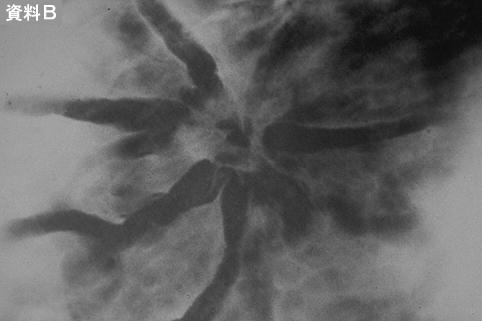

症例提示(所在地,施設名等): 東京都・ 国立がんセンター中央病院と九州がんセンターの共同作成

症例登録日 2014/02/28

画像数 47

検査方法その他